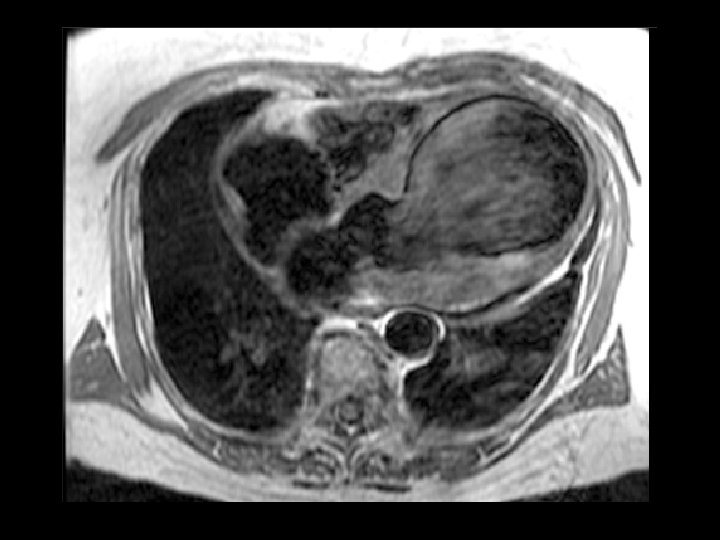

Clínica y diagnóstico o Métodos de diagnóstico por imágenes n Ventriculografía izquierda n Ecocardiografía n TAC n Resonancia magnética

Clasificación o Tres categorías clínico-patológicas: n Aguda n Subaguda n Crónica con formación de un falso aneurisma.

Características del falso aneurisma 1. 2. 3. 4. La pared del falso aneurisma no contiene células miocárdicas. Usualmente de localización posterior. Usualmente tienen un cuello estrecho. Propensos a ruptura